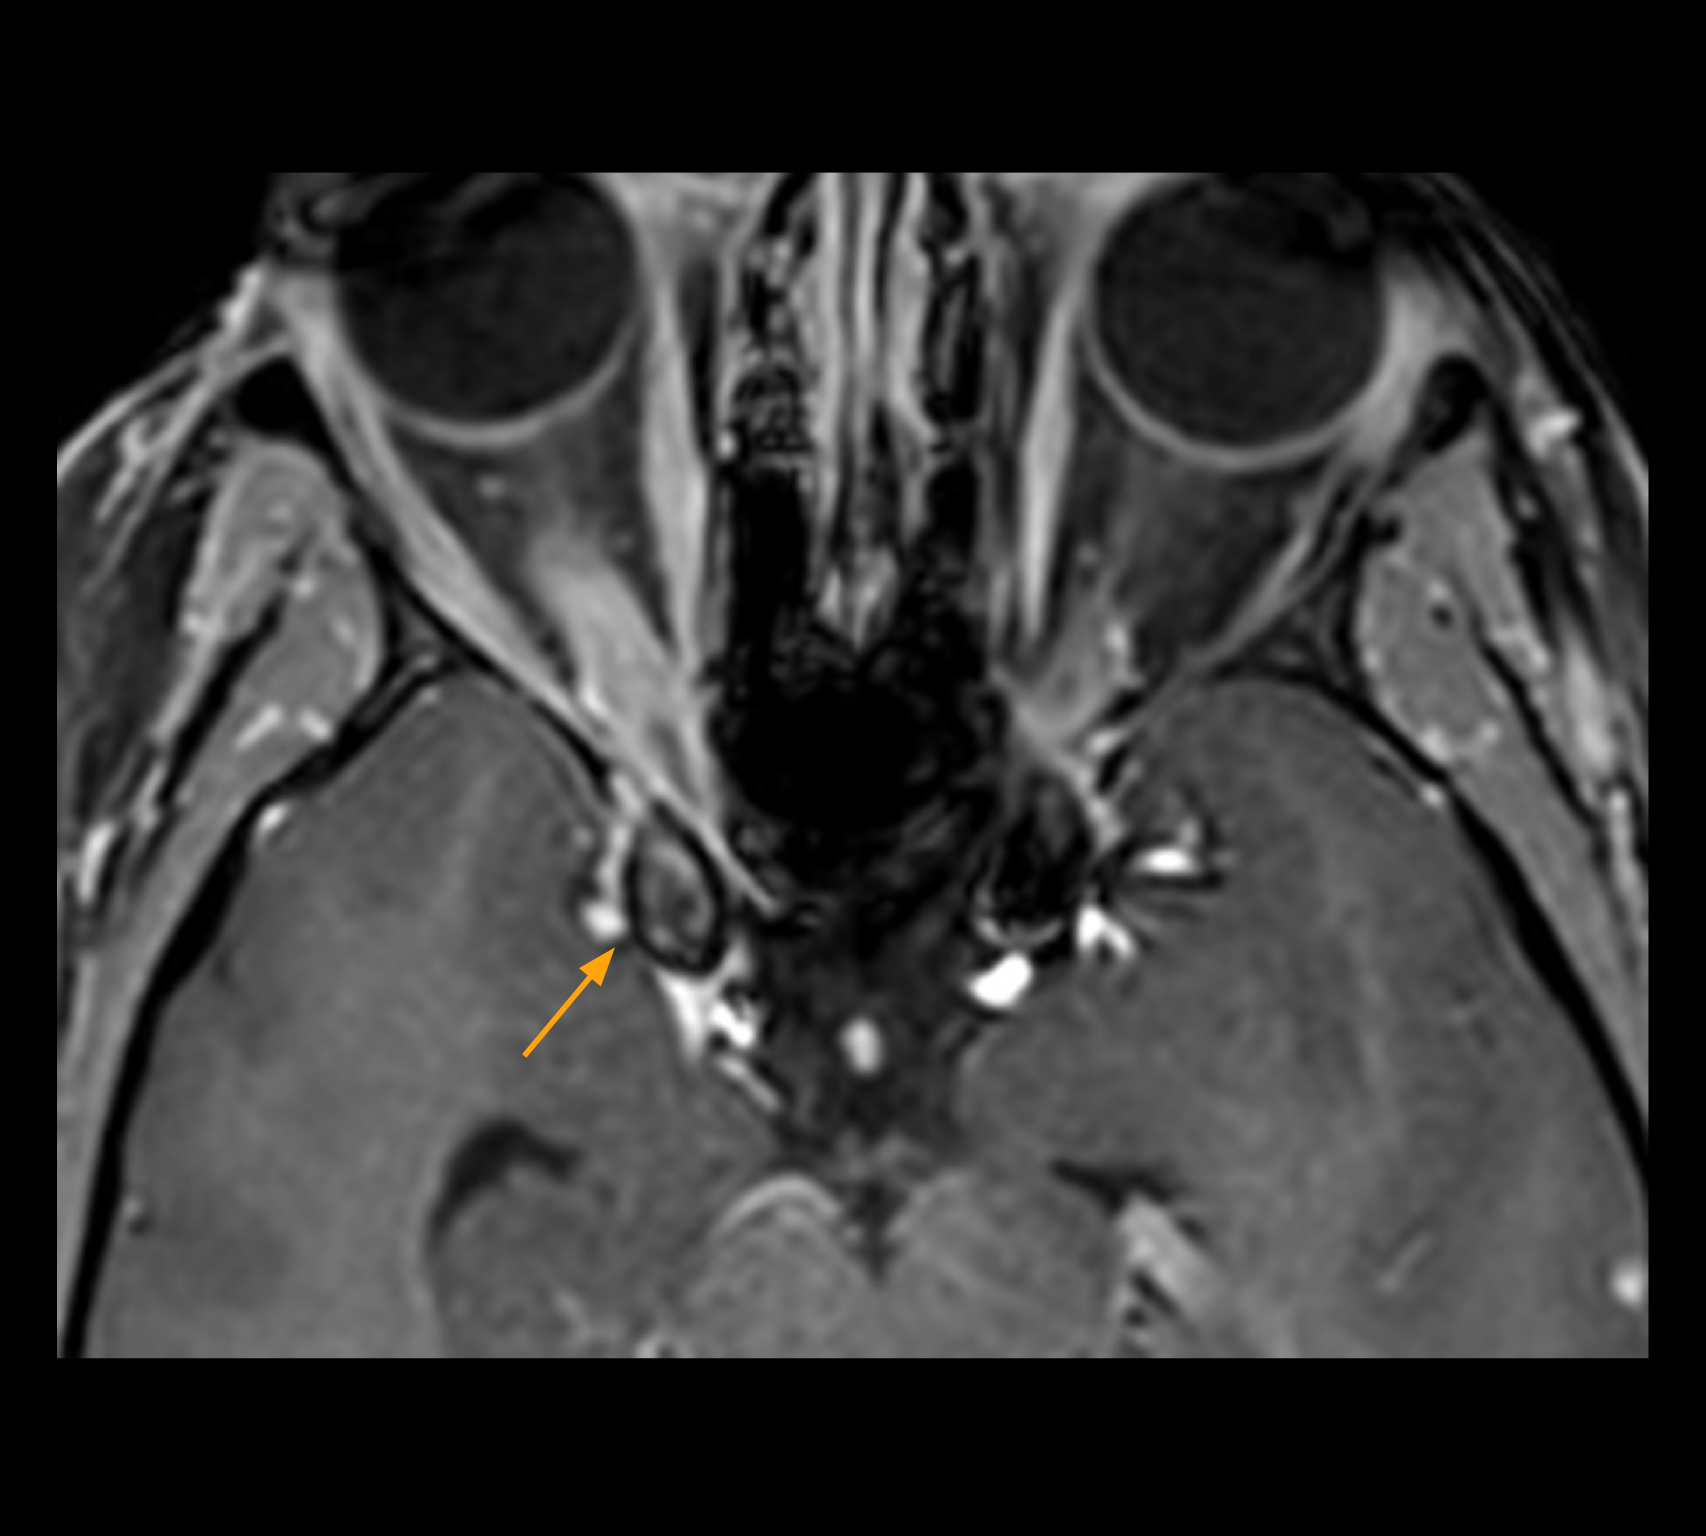

Imaging of the optic nerve sheath

High-resolution MRI impressively demonstrates the compression and narrowing of the right optic nerve in this case of optic nerve sheath meningioma (ONSM). The coronal T2-weighted images show the hyper-intense, half-moon shaped lesion, that is clearly visible in the axial T1W image after contrast injection (right). These imaging findings were so convincing that there sponsible neurosurgeon did not consider a pretherapeutic histological clarification.

High resolution-MRI impressively demonstrates the compression and narrowing of the right optic nerve in this case of optic nerve sheath meningioma (ONSM). The coronal T2-weighted images show the hyper-intense, half-moon shaped lesion, that is clearly visible in the axial T1W image after contrast injection (right). These imaging findings were so convincing that there sponsible neurosurgeon did not consider a pretherapeutic histological clarification.